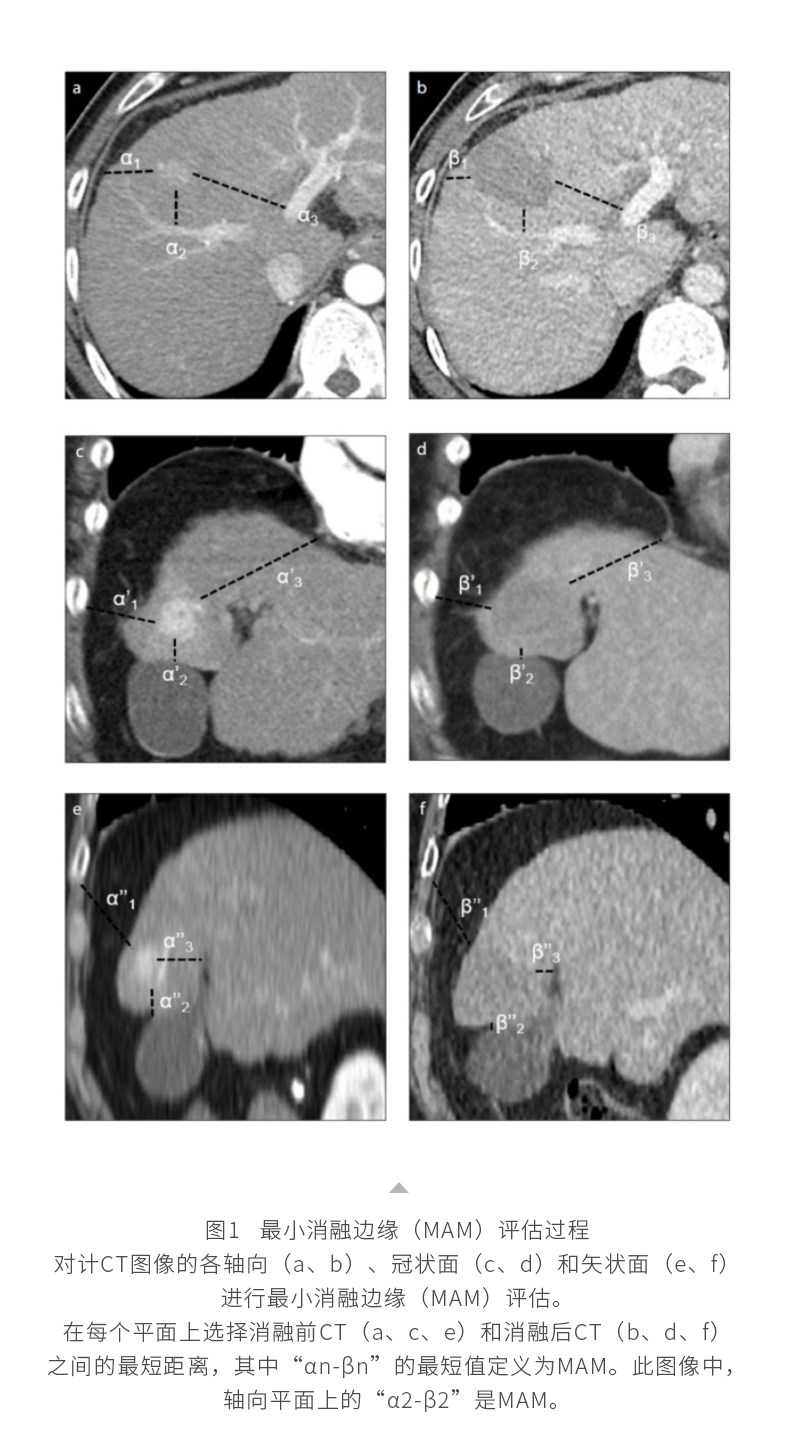

微波消融系統(tǒng)